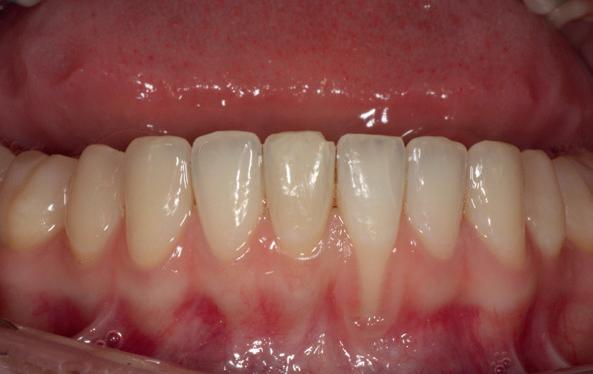

Na afronding van de eerste twee behandelstappen werd parodontale stabiliteit bereikt, zoals waarneembaar op de parodontiumstatus en (röntgen)foto’s (afbeelding 6, 8). De patiënt toonde aantoonbare verbetering in mondhygiëne (afbeelding 4) en bleef gemotiveerd om de behandeling voort te zetten.

4. Lichtfoto na infectie controle